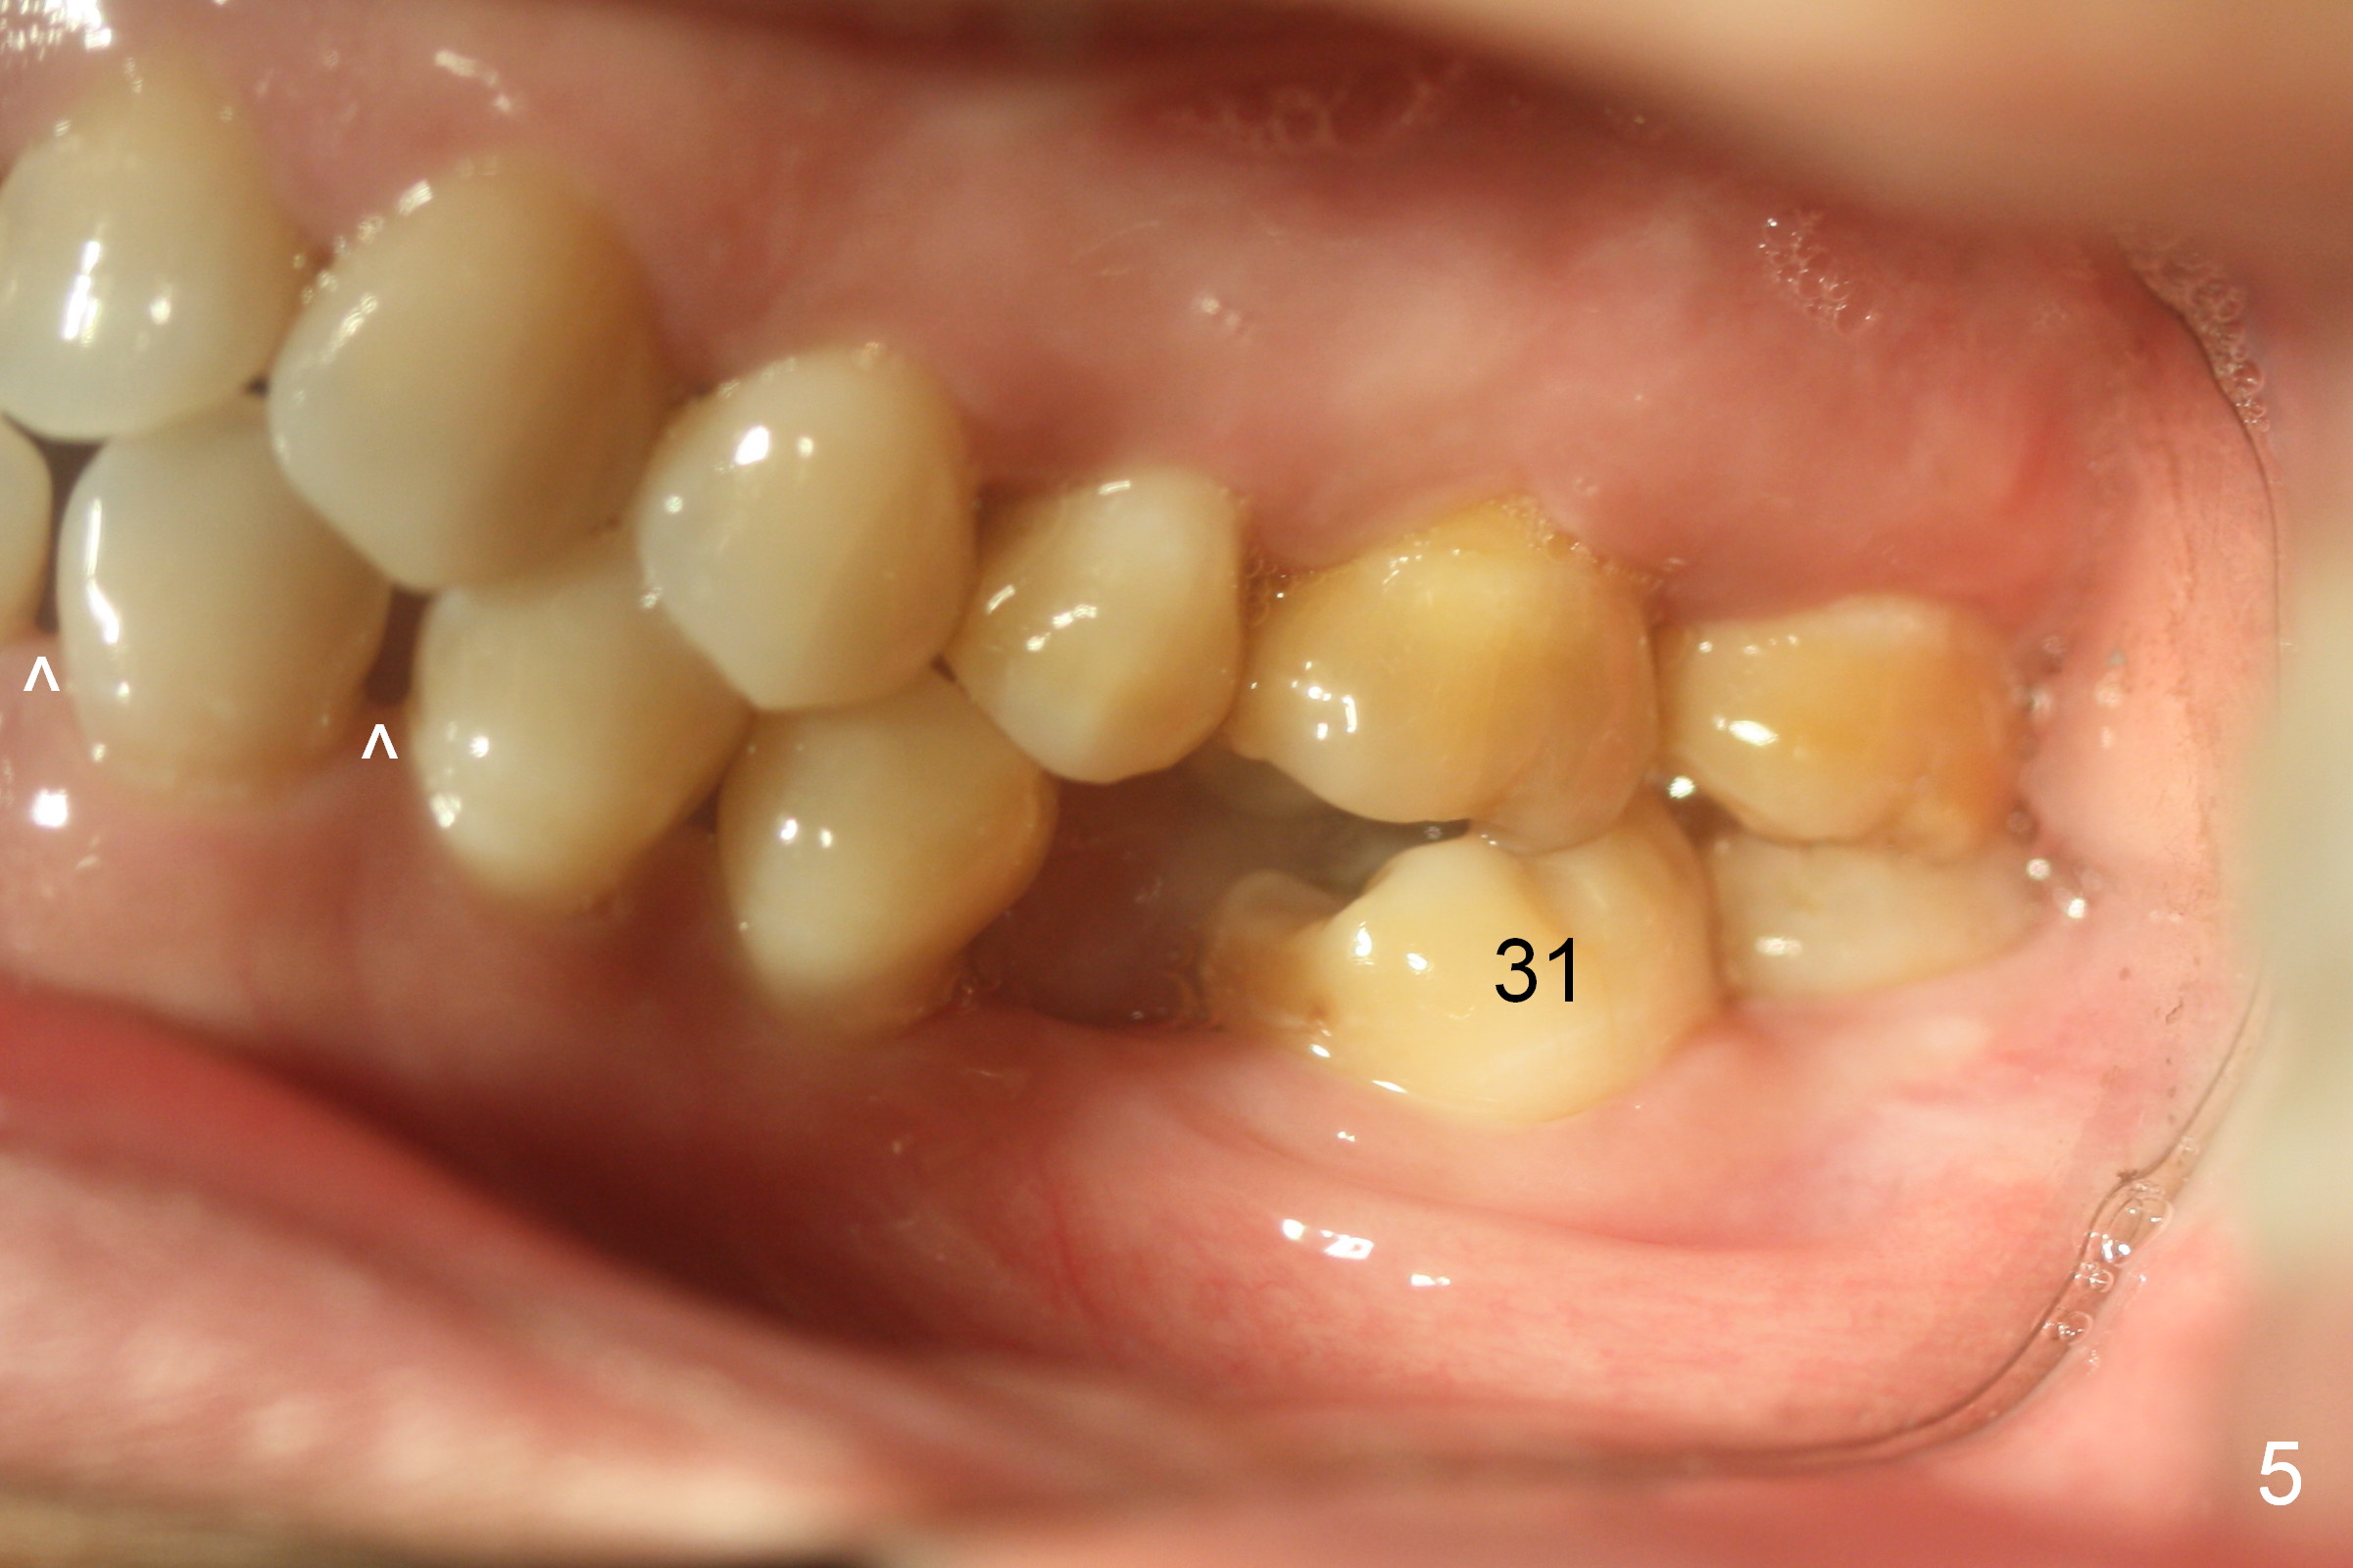

Show the patient that the tooth #31 is severely mesially tilted with reduction in the mesiodistal width for implant placement (Fig.5,7). The tooth #32 is severely malpositioned (linguoversion, Fig.6). It is extremely difficult to gain space for the implant without #32 extraction.